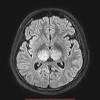

Lesions similar to cytotoxic edema, and lesions similar to vasogenic edema. Seizure, altered sensorium, fever frontal and temporal lobes, rarely extratemporal t2 hyperintensity, restricted diffusion, sometimes. Herpes encephalitis is the most common sporadic encephalitis in the united states and other industrialized countries .occurring as either a primary infection with herpes simplex virus or as a reactivation of latent virus, herpes encephalitis causes significant morbidity and mortality .early intervention with acyclovir significantly improves outcome; The clinical syndrome is often characterized by the rapid onset of fever, headache, seizures, focal neurologic signs, and impaired consciousness 1 . Having said that, mri with contrast is considered the most sensitive imaging modality, and findings are present in over half of individuals 8. The patients with the former type of lesions had fulminating disease, and were in severe clinical condition. Herpes simplex encephalitis occurs as 2 distinct entities: 4 it was found that, rather surprisingly, varicella zoster virus (vzv), the cause of chickenpox and herpes zoster, was the most frequently detected virus at 29%, with hsv and enteroviruses accounting for 11% of cases. Two subtypes are recognized which differ in demographics, virus, and pattern of involvement. (1)department of radiology, ankara numune education and research hospital, ankara, turkey. Neonatal herpes simplex encephalitis is caused by vertical transmission of infection during passage from birth canal with diffuse cerebral involvement within the first month after birth; As the older term limbic encephalitis implies, the most common location of involvement is the mesial temporal lobes and limbic systems, typically manifested by cortical thickening and increased t2/flair. In patients with herpes encephalitis, two distinct types of diffusion imaging findings (on b =1000 s/mm 2 images, and adc maps) were noted:

We present mri findings of two cases of herpes simplex encephalitis (hse) confirmed by pcr analysis, focusing on the serial changes after acyclovir therapy: 4 it was found that, rather surprisingly, varicella zoster virus (vzv), the cause of chickenpox and herpes zoster, was the most frequently detected virus at 29%, with hsv and enteroviruses accounting for 11% of cases. mri findings of herpes simplex encephalitis. For viral infection of the meninges, please refer to the general article on viral meningitis, and, for a broad view on the curriculum of infections of the central nervous system, refer to cns. The patients with the former type of lesions had fulminating disease, and were in severe clinical condition. The kappa value for interobserver agreement on rating the scans as normal or abnormal was good (0.65) for ct and moderate (0.59) for mri. Noguchi t, yoshiura t, hiwatashi a, et al. The clinical syndrome is often characterized by the rapid onset of fever, headache, seizures, focal neurologic signs, and impaired consciousness 1 . The patients with the former type of lesions had fulminating disease, and were in severe clinical condition. Specific diagnosis often requires pcr. As the older term limbic encephalitis implies, the most common location of involvement is the mesial temporal lobes and limbic systems, typically manifested by cortical thickening and increased t2/flair. In patients with herpes encephalitis, two distinct types of diffusion imaging findings (on b =1000 s/mm 2 images, and adc maps) were noted: A recent study in finland also used pcr to detect various viruses in the csf of over 3000 patients who had infections of the cns including encephalitis, meningitis, and myelitis.

Specific diagnosis often requires pcr. Normal mr imaging findings (type 1, 53% of patients), isolated hippocampal involvement (type 2, 13%), other brain lesions without hippocampal involvement (type 3, 13%), and other brain lesions with hippocampal involvement (type 4, 21%). In patients with herpes encephalitis, two distinct types of diffusion imaging findings (on b =1000 s/mm 2 images, and adc maps) were noted: Watershed distribution ischemia in areas remote from the primary herpetic lesions may be seen. article in japanese yoshioka a, hirose g, tsukada k, oda r, kosoegawa h.